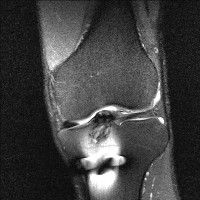

무릎 mri 간단히 봐주실 수 있으시나요 ㅠㅠ

안녕하세요 8년전 십자인대 수술하고 최근 무리한 운동에 무릎 불편감이 생겨서

mri 찍었습니다.

진단결과는 첫 찍은 병원에서 활액막염 이라는 진단을 받았습니다. 혹시 봐주실 수 있으실까요?

올라온 MRI가 단편적이라서 정확한 진단에 어려움이 있지만 십자인대에는 큰 이상이 있지는 않은것 같으며, 무릎관절내 물이 있는 것으로 보아 활액막염의 진단이 맞을 것 같습니다.

하지만 단편적인 영상이기 때문에 촬영병원에서 정확한 판독지 등을 받으시는 것이 좋겠습니다.